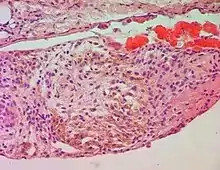

In chronic pulmonary edema, alveolar septa become thick and fibrous, again increasing pressure on alveolar capillaries and resulting in leakage of red blood cells which undergo phagocytosis by alveolar macrophages.